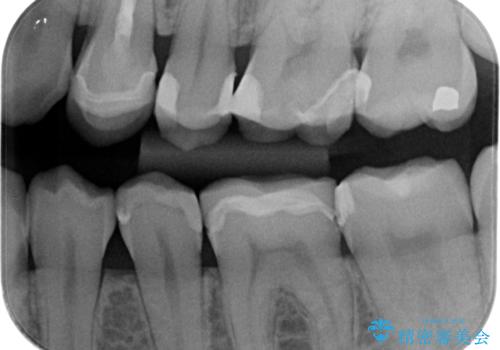

精度の低い詰め物のやり替え

- セラミックのつめものの精度が低かったためやり直しを行いました。

歯の高さがなく、またセラミックアンレーは割れるリスクが高いため、セラミックのアンレーとはせず、クラウンとし、さらに割れにくいようにヴェレッツァクラウンとしました。

- 合計 17.6万円(内訳 左下7:e-max インレー 7.7万円、左下6:セラミッククラウン(ヴェレッツア 8.8万円)、仮歯 1.1万円)費用は治療当時の料金となります

裏側の歯ブラシも当たっておらずプラークが多く付着していたため合わせて歯磨き練習も行いました。